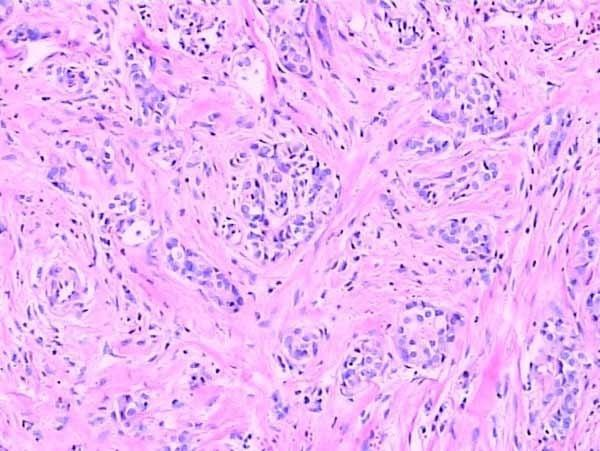

然而,盡管冰凍切片在制片速度上具有優(yōu)勢(shì),但在組織結(jié)構(gòu)保持方面,石蠟切片卻更勝一籌。由于石蠟切片經(jīng)過多種固定劑處理,能夠更好地保持組織的原有結(jié)構(gòu)和形態(tài),有利于科研人員對(duì)組織進(jìn)行更精細(xì)的觀察和分析。而冰凍切片雖然能夠快速固定組織,但在一定程度上可能會(huì)破壞細(xì)胞的細(xì)微結(jié)構(gòu)。

石蠟切片

此外,在染色性能方面,兩種切片技術(shù)也各有千秋。石蠟切片適用于多種染色技術(shù),如H&E染色等,能夠清晰地展示組織的細(xì)胞結(jié)構(gòu)和形態(tài)。而冰凍切片則更多地應(yīng)用于免疫組化和原位雜交等特殊染色技術(shù),為科研人員提供了更多維度的觀察手段。